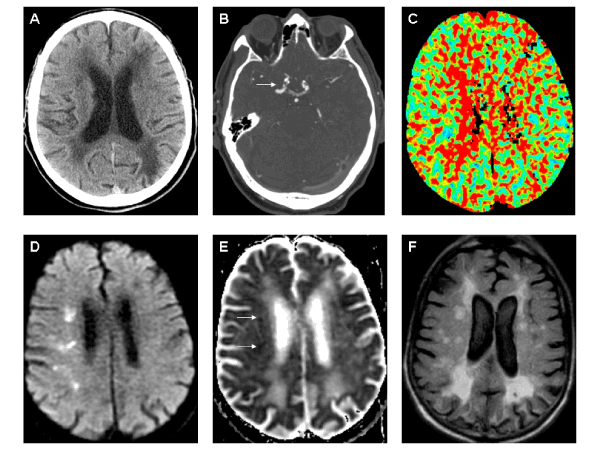

| Figure 1: A. Non-contrast computed tomography (CT) scan showed bilateral periventricular and subcortical hypodensities suggestive of remote small vessel ischemia. An ill-defined right frontal subcortical hypodensity and an old left posterior parietal infarct were also appreciated. B. CT angiography identified bilateral right greater than left supraclinoid calcified plaque with moderate to severe right-sided stenosis (white arrow). C. CT perfusion scan showed prolonged mean transit time and mild increased cerebral blood volume (not shown) in the right subcortical middle cerebral artery territory. D-E. Diffusion weighted imaging and apparent diffusion coefficient scans showed restricted diffusion (arrows) in right subcortical fronto-parietal regions. F. Axial fluid attenuated inversion recovery (FLAIR) imaging revealed bihemispheric periventricular and subcortical increased signal, diffuse sulcal widening with mild global atrophy, associated encephalomalacia in left posterior parietal region, and right subcortical increased signal corresponding to some of the restricted diffusion sites. Note: all images displayed using radiographic convention. |